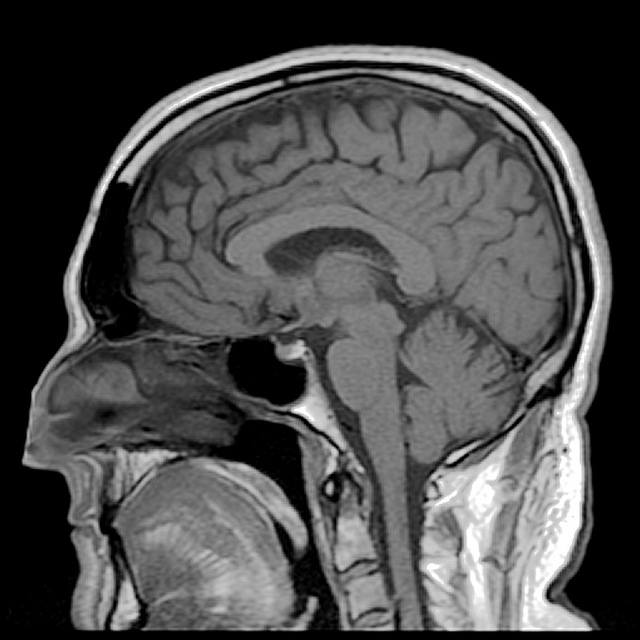

Structure of the brain: an overview

The brain is shaped like two fists standing side by side on a single wrist. The ‘wrist’ is the brain stem, connecting the brain to the spinal column, and the ‘fists’ constitute the left and right hemispheres of the largest part of the brain, the cerebrum. At the back of the brain, below the cerebrum, is the cerebellum. Within each of these parts are specific regions that control specialised functions. Let’s take a look at each section in a bit more detail.

The cerebrum

The cerebrum is the largest and, for most people, the most easily recognisable part of the brain. From an evolutionary perspective, it is also the newest part. It’s in this section that processes such as perception, decision-making, thought, judgement and imagination occur.

The cerebrum has an outer layer known as the cerebral cortex. The largest part of this layer is known as the neocortex (Latin for ‘new bark’), and is composed of six thin layers of neuron cell bodies and non-neuron brain cells called glial cells (more on these later). Their slightly grey colouring is what gives this part of the brain the term ‘grey matter’. The cerebral cortex is arranged in distinctive folds.

These ‘folds’ or wrinkles serve an important purpose. They effectively increase the surface area of the brain, thereby increasing the number of neurons within it and, at the most basic level, more neurons = more connections = a more efficient brain. In fact, the cortex is so heavily folded that if you were to spread it out, it would cover 0.23 square metres. Human brains are wrinklier than the brains of any other animal, a key factor in our higher intelligence levels.

Despite being just a few millimetres thick, the cerebral cortex constitutes 40 per cent of the entire brain mass.

A deep channel divides the cerebrum into two unique halves, or hemispheres (often colloquially referred to as the left and right brain), which communicate with each other via a band of nerve fibres called the corpus callosum. The right side of the brain controls movement in the left side of the body and the left hemisphere controls the right side of the body.

The cerebellum

The cerebellum is found at the back of the brain near the base, tucked beneath the cerebral hemispheres. Sometimes referred to as the ‘little brain’, it contains both grey matter (made up of cell bodies, dendrites and axon terminals of neurons) and white matter (made mostly of glial cells and myelinated axons GLOSSARY myelinated axonsAxons surrounded by a fatty white substance known as myelin. Myelin is essential for the proper functioning of the nervous system. ). The cerebellum works to transmit information to and from the spinal cord and to other parts of the brain.

Physically, the cerebellum is the second-largest part of the brain. Although accounting for only 10 per cent of the brain’s volume, it contains over half of the total number of neurons (specialised cells that transmit information via electrical signals). Like the cerebrum, the cerebellum is also made of two hemispheres, though its folded outer layer (cerebellar cortex) has smaller, finely spaced parallel grooves as opposed to the larger, more irregular folds of the cerebral cortex.

The brain stem

The brain stem connects the brain with the spinal cord and, although it is one of the most basic parts of the brain, it’s one of the most important for ensuring the body’s survival, controlling basic bodily functions such as breathing, swallowing, consciousness and blood pressure. Any damage to the brain stem is usually serious and life threatening.

The brain stem is a tube-shaped mass of nervous tissue, measuring around 8 centimetres in length, which, as it ascends from the spinal cord, becomes more complex in both its internal and external structures.

It is situated at the base of the brain, above the spinal cord and below the cerebrum, and has three primary functions: 1) it relays information from the brain to the body and vice versa, via the brain stem, 2) it gives rise to cranial nerves, and 3) it has integrative functions including control of the cardiovascular system, pain sensitivity, respiration and consciousness.

The brain stem consists of the midbrain, pons and medulla.